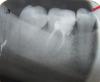

-Vera- Опубликовано 5 октября, 2011 Автор Поделиться Опубликовано 5 октября, 2011 (изменено) Вот один из снимков, сделанных 3 дня назад. К сожалению, плохо видно, это кусочек панорамного снимка, другие не отдали. http://i044.radikal.ru/1110/c7/0fff72abe787.jpg Изменено 5 октября, 2011 пользователем -Vera- Ссылка на комментарий

ger_berra Опубликовано 5 октября, 2011 Поделиться Опубликовано 5 октября, 2011 (изменено) Снимок неудовлетворительного качества.Поэтому сказать,что там с каналами с точностью нельзя.Пломбу при значительном разрушении коронки ставить нельзя.Нужно протезирование.У Вас пломба на контакте с 5-м неровная,имеются зазоры.Там забивается пища,присоединяются микробы полости рта,получается хроническое воспаление десны и,как следствие, боль. Изменено 5 октября, 2011 пользователем ger_berra Ссылка на комментарий

ger_berra Опубликовано 5 октября, 2011 Поделиться Опубликовано 5 октября, 2011 На первом снимке тоже плохо видно? по словам врача, каналы не трогали, т.е. они уже больше 3-х лет так запломбированы. Поясните все же, пожалуйста, что там могло (и могло ли) возникнуть (я имею ввиду воспаление). не совсем понятно, что нельзя ставить: пломбу или коронку? Уже дважды ставили пломбу на бОльшую часть зуба. Так как вариант, возможно ли просто заменить пломбу, чтоб была ровная и не на контакте?Судить о качестве лечения каналов Вашего зуба по такому снимку невозможно(снимок плохого качества).Также невозможно на нём разглядеть ,есть ли воспаление или нет.Воспаление может возникнуть из-за попадания слюны в зуб во время обработки каналов,из-за неправильной или недостаточной обработки инструментами и медикаментами,плохой пломбировкой.У нормального здорового зуба тоже есть коронка(это то,что находится во рту над десной),которая из-за кариеса разрушается и на неё ставят пломбы.Когда эта коронка сильно разрушается ,её покрывают искусственной коронкой(металлокерамикой,например),а не пломбируют.Большие пломбы могут скалываться и привести к перелому зуба.В Вашем случае НЕ НУЖНО менять пломбу.НУЖНО ПРОТЕЗИРОВАНИЕ.Удачи! Ссылка на комментарий